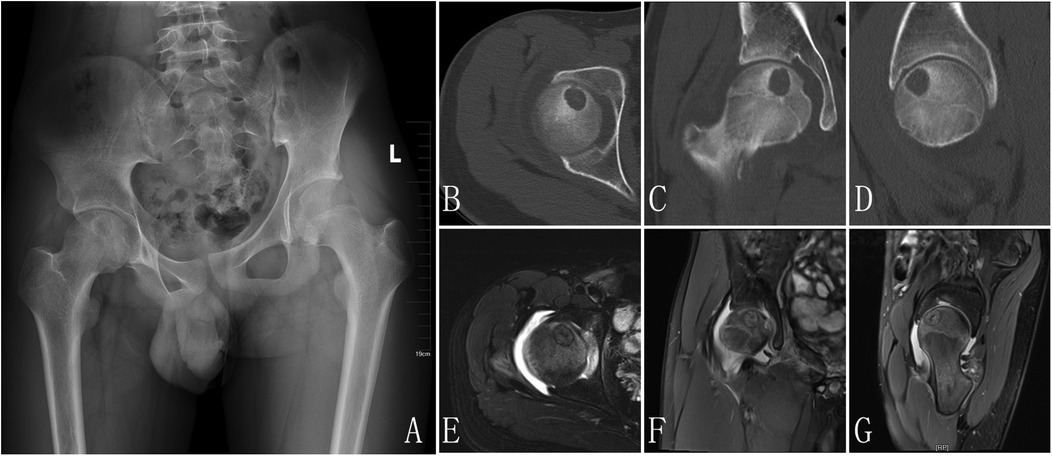

Radiology examination: (1) x-ray: A roundish, slightly hypoattenuating shadow measuring approximately 17 mm in diameter is observed in the region of the right femoral head (Figure 1A) CT: A well-defined, round osteolytic lesion measuring approximately 12 mm  ×  16 mm is identified within the right femoral head on coronal imaging. It demonstrates mild hyperdensity with a surrounding sclerotic margin (Figures 1B–D) MRI: On T1WI and T2WI, a patchy area of mixed slightly high signal intensity is noted in the right femoral head, with clear margins and dimensions of approximately 12 mm  ×  16 mm. Patchy areas of high signal intensity are also present on PDWI in the right femoral head-neck junction and acetabulum. The synovium of the right femoral head is thickened, with associated joint effusion. Additionally, patchy high-signal-intensity regions are observed in the surrounding soft tissues on PDWI (Figures 1E–G).

Figure 1

X-ray and MRI scans of the pelvis and hip joint showing multiple angles in seven panels labeled A to G. Each panel displays different aspects of bone and soft tissue, highlighting the femur and pelvis structures.

Figure 1. X-ray pre-op: a slightly hypoattenuating shadow was observed in the region of the right femoral head (A), CT: a well-defined, round osteolytic lesion is identified within the right femoral head on coronal imaging. It demonstrates mild hyperdensity with a surrounding sclerotic margin (B–D), MRI: a patchy area of mixed slightly high signal intensity is noted in the right femoral head, with clear margins. Patchy areas of high signal intensity are also present on PDWI in the right femoral head-neck junction and acetabulum. The synovium of the right femoral head is thickened, with associated joint effusion. Additionally, patchy high-signal-intensity regions are observed in the surrounding soft tissues on PDWI (E–G).